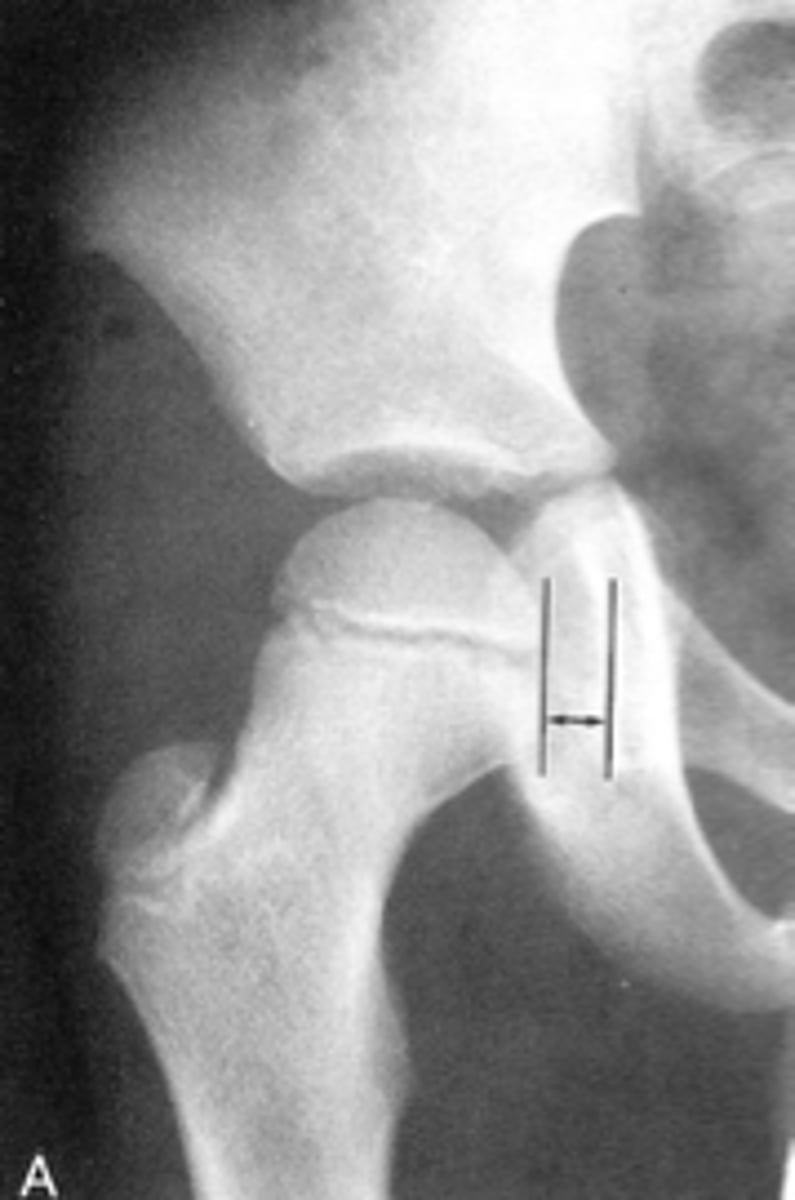

- AP hip

- Frog-leg (lateral) hip

State the standard unilateral hip projections

Unilateral AP hip

ID standard unilateral hip projection

Frog-leg (lateral) hip

Kohler's teardrop distance

ID measurement line

- AP pelvis

What views are needed to see Kohler's teardrop distance?

- Medial margin of femoral head

- Lateral border of teardrop

Kohler's teardrop distance landmarks

6-11 mm

Normal Kohler's teardrop distance measurement

2 mm

The normal Kohler's teardrop distance is 6-11 mm, and there should be no greater than a _____ difference when comparing to the contralateral side

Hip joint effusion

Clinical significance of an enlarged Kohler's teardrop distance

Waldenstrom's sign

What sign indicates an enlarged Kohler's teardrop distance?

- Accentutation of the normal limits

Intracapsular swelling/joint effusion

Waldenstrom's sign is usually an indication of _____

Inflammatory arthritis

Clinical significance of a small Kohler's teardrop distance

Hip joint space width

ID measurement

Superior, axial, medial joint spaces (SAM)

Hip joint space width landmarks

3-6 mm

Normal superior hip joint space width

3-7 mm

Normal axial hip joint space width

4-13 mm

Normal medial hip joint space width

Joint effusion

Clinical significance of a wide hip joint space

Arthritis

Clinical significance of a narrow hip joint space